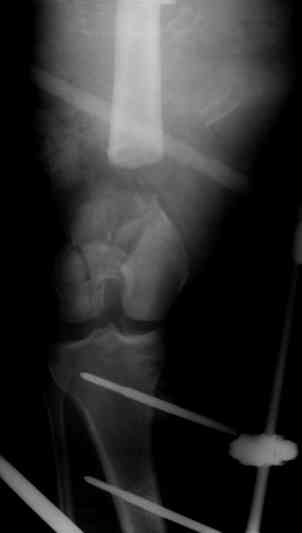

Больной 27 лет, мотоциклист. Поступил 23.04.10

ДЗ. О. перелом н.з левого бедра Gustillo 3b (c повредрение бедренной вены),

О.Правого бедра Gustillo 2, з. фрагментарный перелом левой голени.

При поступлении Hb 66 ISS 40, фиксация стержневыми аппратами, сосудистые хирурги выполнили шов вены. Выполена резекция бедренной кости 9 см

Вопрос: что делать с левым бедром? Учитывая внутрисутавной характер перелома, дефект бедра 9 см.